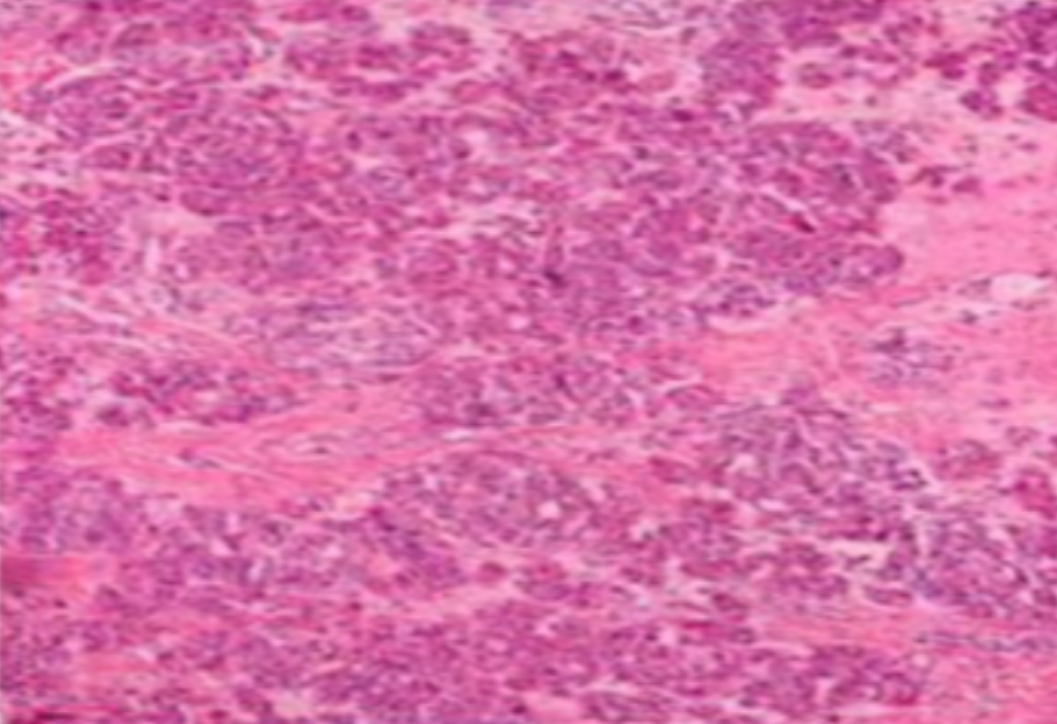

HE染色,全称苏木精-伊红染色法(Hematoxylin and Eosin staining),是最常见的组织切片染色技术之一,用于在显微镜下观察和分析组织或细胞的结构和形态。虽然HE染色是最常见且最基础的染色技术之一,😭但在实验过···

HE染色,全称苏木精-伊红染色法(Hematoxylin and Eosin staining),是最常见的组织切片染色技术之一,用于在显微镜下观察和分析组织或细胞的结构和形态。

虽然HE染色是最常见且最基础的染色技术之一,😭但在实验过程中,很容易出现各种情况导致染色切片质量参差不齐。所以,小编根据以往实验经验,给大家整理归纳出了15个HE染色中的常见问题,还包含问题原因分析以及解决方法哦~

形成原因:切片经梯度乙醇处理后没有完全脱水,导致二甲苯透明、中性树胶封固后残留大量水分。 解决方法:首先移去盖玻片,用二甲苯溶解封固剂如中性树胶,再将切片置入无水乙醇内,待切片重新脱水完全后,用二甲苯透明处理,中性树胶封固。要注意所有用于脱水和透明的液体,在使用一定时间后,应及时更换。 二、细胞核呈红、棕色 形成原因:苏木精染色液过度氧化,切片在苏木精染液染色后返蓝不足。 解决方法:每次染色之前检查苏木精染色液的染色能力,发现苏木精染色液氧化过度应及时更换。此外,切片经苏木精染色后,要给切片以足够的蓝化时间,蓝化过程可用流水、温水、弱碱性溶液(如稀氨水或0.2%碳酸氢钠)等处理。 三、切片在脱蜡后出现大片白色斑点 形成原因:由于烤(烘)片温度太低,切片上的组织蜡膜在脱蜡前没有充分烤(烘)融化。或是因为切片在二甲苯液中停留时间不足,或二甲苯使用过久,造成的脱蜡不彻底。 解决方法:若是由于切片烤(烘)温度低所致,可以先用二甲苯去除切片上的封固胶,然后重新用二甲苯脱去切片上的石蜡,再进行后续染色。若是由于切片在脱蜡的二甲苯中停留时间不足或脱蜡二甲苯使用过久浓度不足所致,则需将切片退回到二甲苯中,停留较长时间,或更换二甲苯液体重新脱蜡,再入乙醇重新脱二甲苯,入0.5%盐酸水溶液褪色后,重新HE染色。 四、细胞核苍白暗淡,即苏木精染色太淡 形成原因:切片在苏木精染色液停留时间太短;苏木精染色液过度氧化,失去染色能力,不能再继续使用;分化步骤处理时间过长;固定不及时。此外值得注意的是,若骨组织细胞核暗淡,大多是脱钙过度造成的。 解决方法:切片重新染色。如果组织在酸性固定液(如Zenker、Bouin)或非中性缓冲甲醛液固定时间过长,细胞核染色能力将减弱,需增加其在苏木精染色液的时间,或用一些方法增加组织的嗜碱性,以改善细胞核的着色。例如,上述组织玻片可以使用Weigert铁苏木精染色液。如果组织是用Zenker液固定的,可将切片脱蜡后放在5%碳酸氢钠溶液3~4h,流水冲洗5min后染色。如果组织是用Bouin液固定的,可将切片脱蜡后放在5%碳酸锂1h,流水冲洗10min后染色。 五、细胞核过染,苏木精染液占据了细胞质 形成原因:玻片在苏木精染色液停留时间过长,或是切片太厚、分化步骤时间太短。 解决方法:如果不是因为切片太厚(用显微镜仔细上下微调,只有一二层细胞核层次),就需将切片进行脱色、漂白、重新染色,适当调整染色和分化时间。但如果确定是由于切片太厚导致的细胞核过染,则需要重新切片。 六、伊红着色淡 形成原因:可能是伊红染液pH值大于5,也可能是蓝化液残留过多,切片太薄,或是切片经伊红染色后在乙醇脱水时间过长。 解决方法:检查伊红染液pH值,必要的话,用乙酸将其调节在4.6~5.0之间,从而使伊红染色色彩艳丽。此外,确保每次蓝化步骤完成后,使用的弱碱性溶液被充分洗去,玻片上没有残留的弱碱性溶液。最后,检查切片的厚度,且脱水时不要让切片在低浓度乙醇中停留时间过长,因为含水多的低浓度乙醇会将切片伊红的颜色分化掉。 七、细胞质过染、分色不足 形成原因:伊红染色液浓度太高,特别是存在焰红燃料、四溴四氯荧光素钠。切片在伊红染色时间过长,或是切片在伊红染色后经乙醇脱水步骤时时间太短,而使乙醇分化伊红的作用不能产生,都能够使细胞质过染。 解决方法:适当稀释伊红染色液,减少伊红染色时间,或使切片在乙醇脱水等步骤时,停留时间相对均匀。同样,也要检查切片的厚度是否合适。 八、切片中出现蓝黑色沉淀物 形成原因:苏木精染色液中的金属膜黏附在玻片上。 解决方法:染色前仔细过滤苏木精染色液,建议使用半氧化苏木精染色液,如Gill苏木精染色液,可以避免过多的金属膜产生。 九、光镜下切片某些区域难以聚焦 形成原因:盖玻片上可能有封固切片的封固剂。 解决方法:移去盖玻片,重新用干净的盖玻片封片。检查切片封片方法,是人工手工封法,还是机器自动封法,如有问题及时调整。 十、封固剂从盖玻片与载玻片之间的缝隙回缩 形成原因:盖玻片弯曲或不平整,或是封固剂含二甲苯过多,稀释过度。 解决方法:移去盖玻片,重新找一张盖玻片,用干净的封固剂封片。如用手工封片法,保证在封固结束时,封固剂容器盖子为紧闭状态。且尽量使用小的容器盛装封固剂,一旦封固剂太黏稠,就可以选择废弃。 十一、细胞核呈灰蓝状态 形成原因:可能由于组织处理温度过高、过热,在液体石蜡中停留的时间过长。或是固定时间太短后,直接在高浓度的乙醇中进行了脱水处理。 解决方法:理论上来说,仅在组织浸蜡步骤才进行加热,组织不能在热蜡液中停留太久。如果由于某些原因不能进行下一步包埋处理,可将组织连同塑料包埋盒一并放置在室温空气中,冷却凝固,以备包埋。待需要包埋时再重新加温直至石蜡融化即可。组织在处理前必须确保固定良好,脱水最好能从低浓度的乙醇开始。 十二、类色素的点状结晶和黑色光滑细胞核 形成原因:这种裸核改变是因为切片封片前放置在空气中的时间太长,以至于二甲苯挥发,切片干燥。 解决方法:移去组织切片上的盖玻片和封固剂,重新处理。将切片水洗数分钟,然后重新脱水、透明、封固。封片过程中要保持组织切片的轻度湿润,尽量不要让其干燥。 十三、染色过淡或过浓 解决方法:如果染色过淡,可以增加染色剂的浓度、延长染色时间或更换新鲜的染色剂;如果染色过浓,则应减少染色剂的浓度或缩短染色时间。 十四、切片出现叠加褶皱 形成原因:新购买的玻片洁净度不够、用镊子撑开切片时操作不够熟练未能平整伸展,或玻片表面有油脂,切片粘贴不牢。另外,烤片时间不足、烤片温度过低或切片过厚造成切片脱落,都会造成重叠或有皱褶的情况。 解决方法:新购买的玻片最好能用硫酸清洁液浸泡一晚,然后流水冲洗干净。在适宜的温度下烤片时间宁长勿短,保证有充足的烤片时间和温度。另外,切片刀要锋利,才能切出厚薄适宜的切片,保证切片不会因为过厚而脱落。 十五、组织残缺不全或有刮划痕迹 形成原因:组织残缺不全是由于切片时修整蜡块时深度不够、组织没有全部暴露于切面。切片的刮划痕迹是由于切片刀的刀锋有缺口、包埋的组织有异物,或是钙化组织、骨组织及包埋石蜡有沙粒造成的。 解决方法:修整蜡块时保证组织块全部暴露于切面,切片时保证切片刀的锋利没刀口。同时在组织取材时去除手术异物和钙化组织。最后,骨组织要完全脱钙,这样可以保证切片的完整和平整美观。 *注:由于实验中导致结果出现误差的原因多种多样,以上内容仅供参考,具体根据实际情况进行判断。